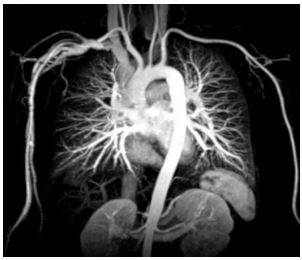

КТ Ангиография грудного отдела аорты и её ветвей с контрастированием

Это такой метод рентгенологической диагностики, с помощью которого можно оценить анатомическое строение и состояние грудного одела аорты и ее ветвей.